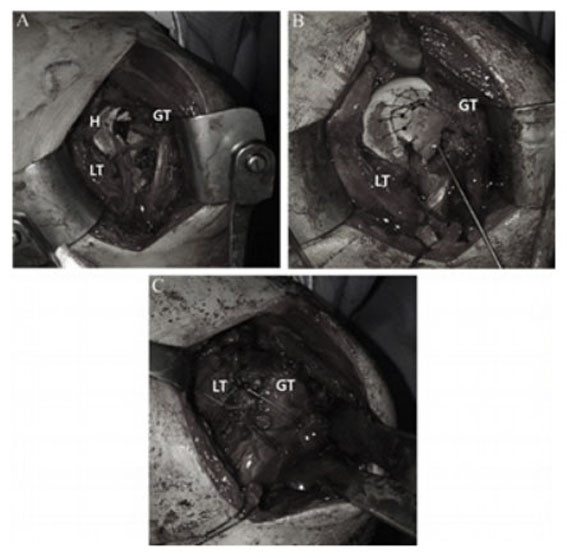

Á¤Çü¿Ü°ú ¼ö¼ú °ü·Ã ±¹Á¦ÇмúÁöÀÎ ¡®Journal of Arthroscopy and Joint Surgery¡¯¿¡ °ÔÀçµÈ ¡®Reverse Hill-Sachs lesion with a greater and lesser tuberosity fracture of the humerus due to posterior shoulder dislocation¡¯ ³í¹®Àº ¾î±ú Å»±¸ ¹× ±¤¹üÀ§ ȸÀü±Ù°³ º´º¯¿¡ ´ëÇÑ Ä¡·á¹ýÀ» ¿¬±¸ÇÑ ³í¹®ÀÌ´Ù.

À̹ø ¿¬±¸¿¡¼ À¯À缺±³¼ö´Â ¾î±ú Å»±¸¿Í µ¿¹ÝµÈ »ó¿Ï°ñ ±ÙÀ§ºÎ °ñÀý ȯÀÚ¿¡°Ô ºÀÇÕ ³ª»ç ¹× ³ª»ç¸ø °íÁ¤¼úÀ» ½ÃÇàÇÏ¿© Áõ»óÀÌ È£ÀüµÇ´Â °á°ú°¡ ³ªÅ¸³µÀ½À» È®ÀÎÇß´Ù.

| | ¡è¡è ¡ãºÀÇÕ ³ª»ç ¹× ³ª»ç¸ø °íÁ¤¼ú <»çÁøÁ¦°ø=õ¾È¾Æ»êÃæ¹«º´¿ø> | ¨Ï ¿Â¾ç½Å¹® | |